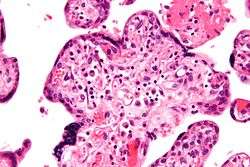

| Micrograph of villitis of unknown etiology. H&E stain. | |

Histomorphologically, VUE is characterized by a lymphocytic infiltrate of the chorionic villi without a demonstrable cause. Plasma cells should be absent; the presence of plasma cells suggests an infective etiology, e.g. CMV infection.